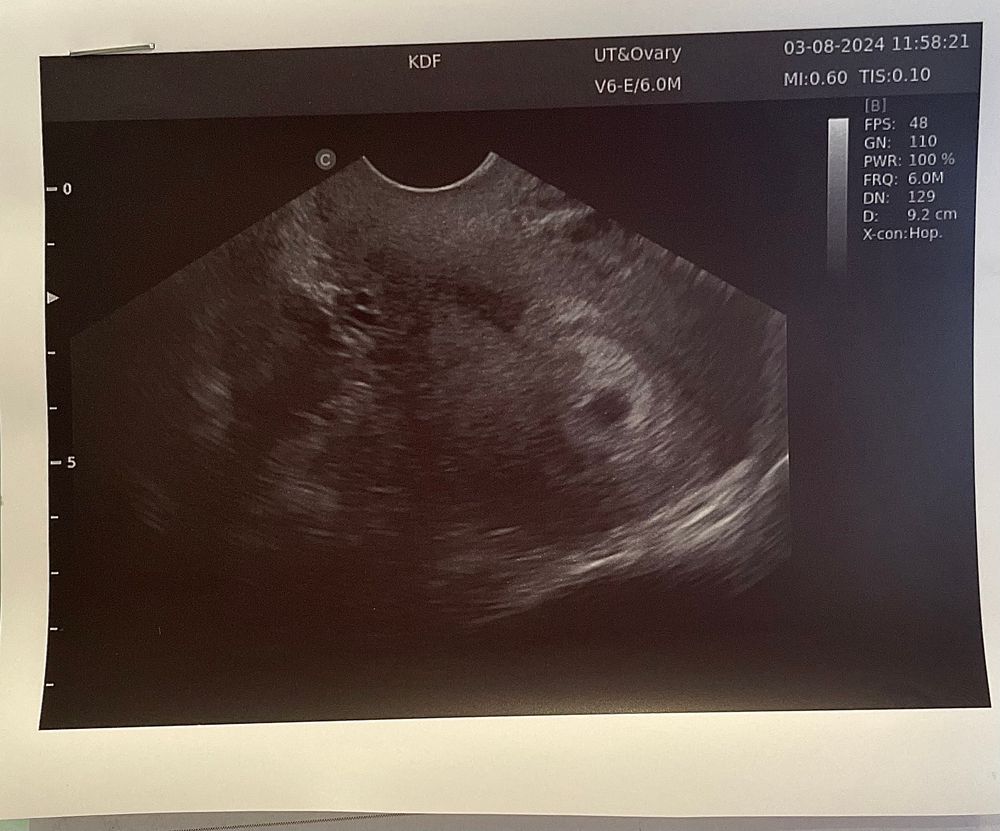

Сегодня 27дпп и первое УЗИ. Плодное яйцо СВД - 7,7мм, внутри пока ничего не разглядели.

Плодное яйцо маленькое. Да и ЖМ уже точно должен быть. Хотя на 27дпп и эмбрион у большинства есть.